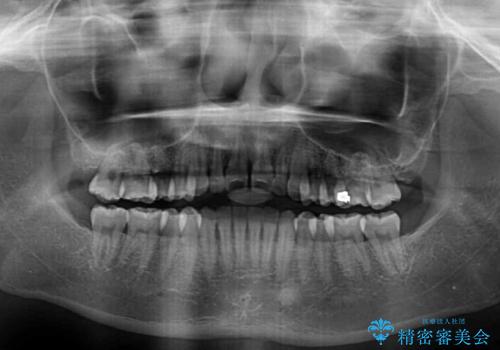

すきっ歯とオープンバイトをインビザラインで改善

- 前歯の上下スペースと前歯の隙間を気にして来院された患者様です。

インビザラインにより上下の前歯の隙間を閉じていくこととしました。

上下の隙間に舌が入り込むことが、すきっ歯やオープンバイトの原因であったため、舌の筋肉のトレーニングも並行して行い、後戻りの抑制を図りました。